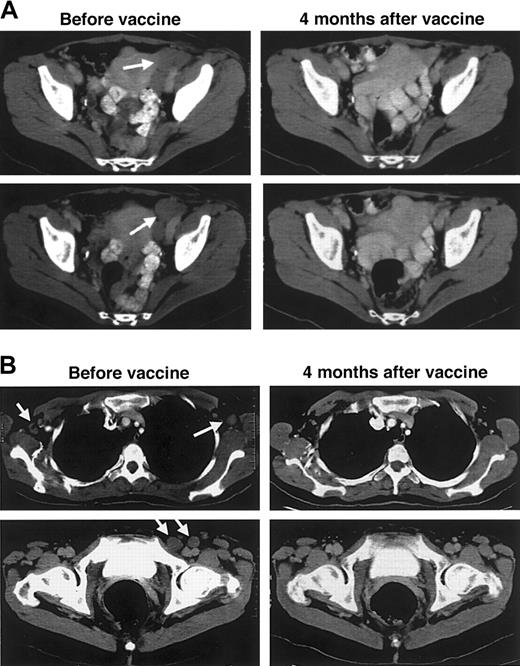

Patients with persistent or relapsed tumors after DC vaccination were offered booster vaccination with Id-KLH protein without DCs, as performed in our previous vaccine trials.7 Biopsy samples were again taken from tumors of 4 patients before revaccination (patients D5, D6, D10, D12). Each was found to have retained expression of surface immunoglobulin heavy and light chains of the same classes found on the original tumor. Therapy consisted of 5 subcutaneous injections of the same Id protein used for DC vaccination yet was coupled to KLH and was emulsified in a chemical adjuvant.7Six patients were treated—5 from the pilot study who had not fully responded and 1 who had a relapse after DC vaccination given during first remission (Table 3). The Id-KLH booster vaccinations were given at different lengths of time after the original DC vaccination series (range, 8-33 months), and all patients had multiple sites of progressive, evaluable tumor. Three of the patients had immune responses to the booster vaccine series; 2 were T-cell responses and one was a humoral response (Table 3). These responses were of the same type (T cell, humoral) and of similar magnitude to those each patient previously mounted to the DC vaccine, though the earlier responses had waned in the interval before boosting. Each of the 3 immune responders also had a corresponding clinical response; one PR lasting 14 months, one CR ongoing at 48+ months, and one CRu lasting 16 months. The latter patient (patient D12), treated 18 months after relapse following DC vaccination given in first remission, had extensive lymphadenopathy involving cervical, axillary, iliac, and inguinal lymph nodes, including a pelvic mass measuring more than 4 × 5 × 6 cm. Bone marrow was also involved. Within 2 weeks of the first injection of Id-KLH, all palpable lymphadenopathy began to rapidly regress, and physical examination results became normal in the next 4 weeks. Normalization of all nodes was documented by CT at 1 and 4 months after the completion of vaccination (Figure6A-B), and the only evidence of tumor was equivocal findings in the bone marrow. At 16 months after vaccination, small recurrent lymph nodes were detected in the right side of the neck. A repeat series of Id-KLH vaccinations (designated vaccine course 3) was then administered, and tumor regression occurred once again, with CR documented 7 months later accompanied by an ongoing Id-specific T-cell proliferative response (Table 3).

Regression of tumors after booster vaccination with Id-KLH + chemical adjuvant.

Patient D12 was given Id-pulsed DC vaccination during first remission after chemotherapy but relapsed 15 months later. Subsequent to the development of widespread disease 18 months later, she was given injections of Id-KLH protein plus a chemical adjuvant. (A) CT images of the pelvis show that bulky left-sided pelvic lymph nodes have completely regressed 4 months after booster vaccinations. (B) Regression of axillary (top panels) and inguinal (bottom panels) lymph nodes after booster vaccinations. Arrows indicate sites of disease before vaccination.